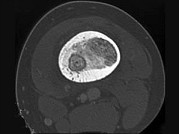

- 单项选择题男,30岁, 左大腿疼痛1年余,夜间或休息加重, 口服止痛药可缓解,结合图像, 最可能的诊断是 ( )

B、骨样骨瘤